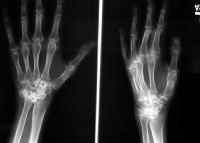

Clinical Example: Rheumatoid arthritis with DRUJ and radiocarpal involvement

Rheumatoid arthritis has many forms of presentation. This patient has bilateral severe radiocarpal and distal radioulnar joint involvement, with relative sparing of the metacarpophalangeal and interphalangeal joints.

Note the spontaneous radiolunate fusion.